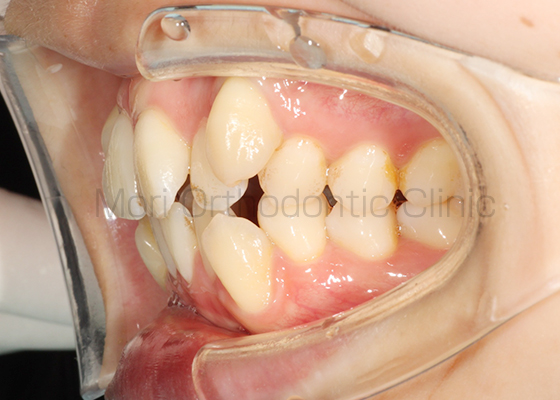

術前